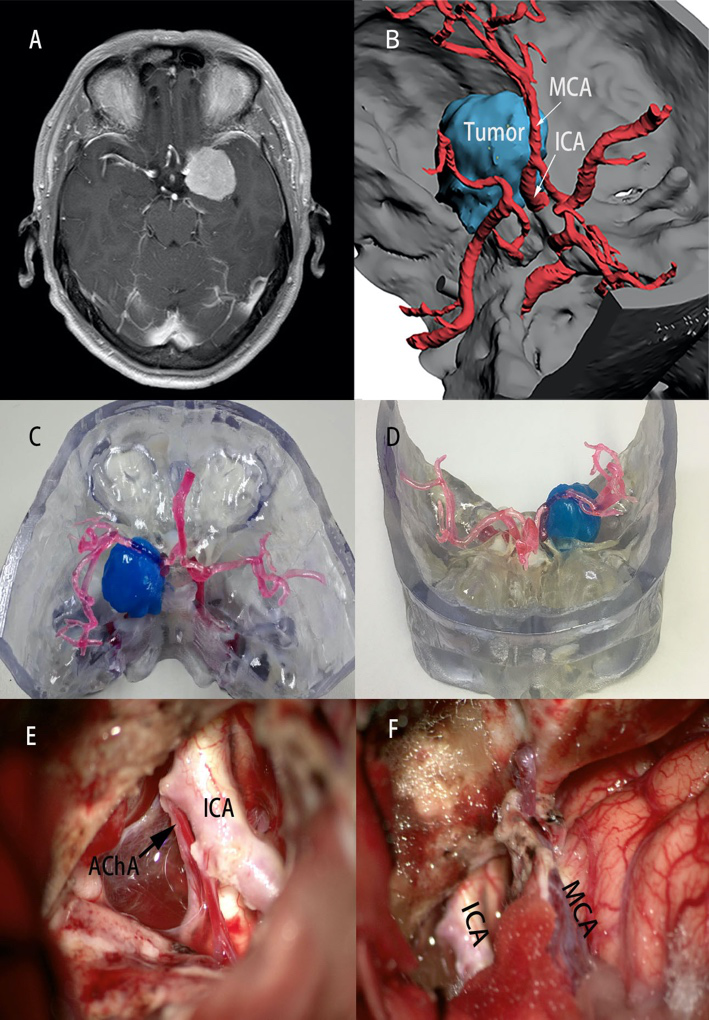

所有病例均通过软件实现了三维立体虚拟现实影像的重建并打印出了三维立体模型。所有的立体模型均清晰地显示出周围组织与颅底肿瘤的相对位置,并且不同组织之间采用不同的颜色标注,明确的显示组织结构关系。对于神经或血管包饶在肿瘤内的病例,我们采用透明材料打印肿瘤形态,可以明显看到肿瘤包饶的血管及神经走行。

颅底肿瘤3D模型展示了颅底肿瘤、神经、血管、颅底情况。根据模型所提供的肿瘤的大小,神经血管包饶或侵犯情况,肿瘤供血动脉的走行及颅底的形态及侵犯范围,确定肿瘤暴露范围。并且通过3D模型,测量相应的骨性标志及骨质磨除范围,在3D模型上进行模拟手术。分析采用不同手术入路下的肿瘤切除程度、神经血管的保护。以最大化保护神经组织和血管为前提,充分暴露肿瘤,争取肿瘤的最大化切除。

在手术时,发挥3D打印模型的优势,采用“逆行切除”手术方法,通过3D模型所提供的肿瘤供血动脉走行路径,首先切断肿瘤的供血动脉,减少肿瘤血供,对于较小的肿瘤,直接离断肿瘤基底,再分块切除肿瘤;对于较大的肿瘤,先进行瘤内减压,再处理肿瘤基底,交替进行,由于已经切断了肿瘤主要供血动脉,所以在切除过程中肿瘤创面只有轻微出血。